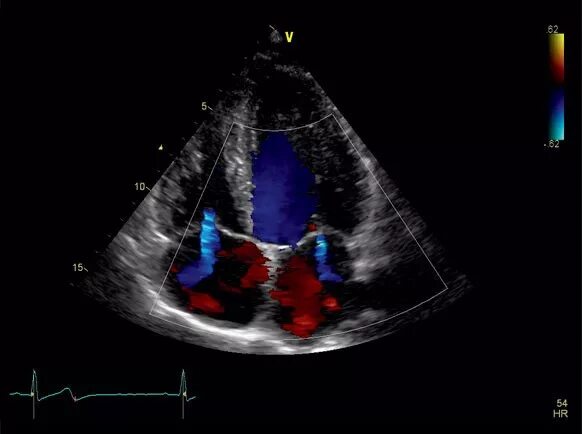

Аортальный стеноз допплер эхокг. допплерография при митральной недостаточности. допплер узи сердца. аортальная регургитация на эхокг.

Аортальная недостаточность эхокардиография. аортальная недостаточность допплер эхокг. недостаточность аортального клапана узи. недостаточность аортального клапана эхокг.

Аортальный стеноз допплер эхокг. митральная недостаточность узи. стеноз аортального клапана эхокардиография. митральный стеноз на узи сердца.